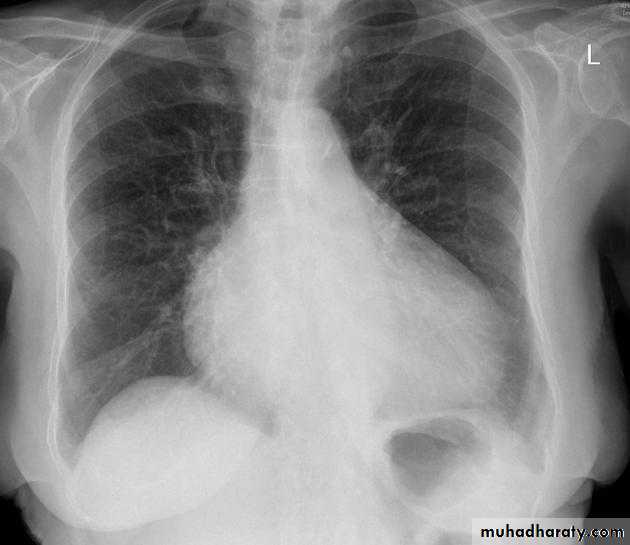

Pulmonary edema is a broad descriptive term and is usually defined as an abnormal accumulation of fluid in the extra-vascular compartments of the lung .

Radiographic features

Septal lines, also known as Kerley lines, are seen when the interlobular septa in the pulmonary interstitium become prominent. This may be because of lymphatic engorgement or edema of the connective tissues of the interlobular septa. They usually occur when pulmonary capillary wedge pressures reach 20-25 mmHg ,

Classification

Kerley A linesThese are 2-6 cm long oblique lines that are <1 mm thick and course towards the hila. They represent thickening of the interlobular septa

Kerley B lines

These are 1-2 cm thin lines in the peripheries of the lung. They are perpendicular to and extend out to the pleural surface . They represent thickened sub pleural interlobular septa and are usually seen at the lung bases.Interstitial pulmonary edema

radiograph include if pressure > 25 mmHg the findings of :

cardiac size/cardio-thoracic ratio: useful for assessing for an underlying cardiogenic cause or associationbat wing pulmonary opacities

presence of peri-bronchial cuffing

septal lines: Kerley lines become more prominent

pleural effusions

pulmonary venous engorgement/pulmonary blood flow distribution upper lobe pulmonary venous diversion

Alveolar pulmonary edema